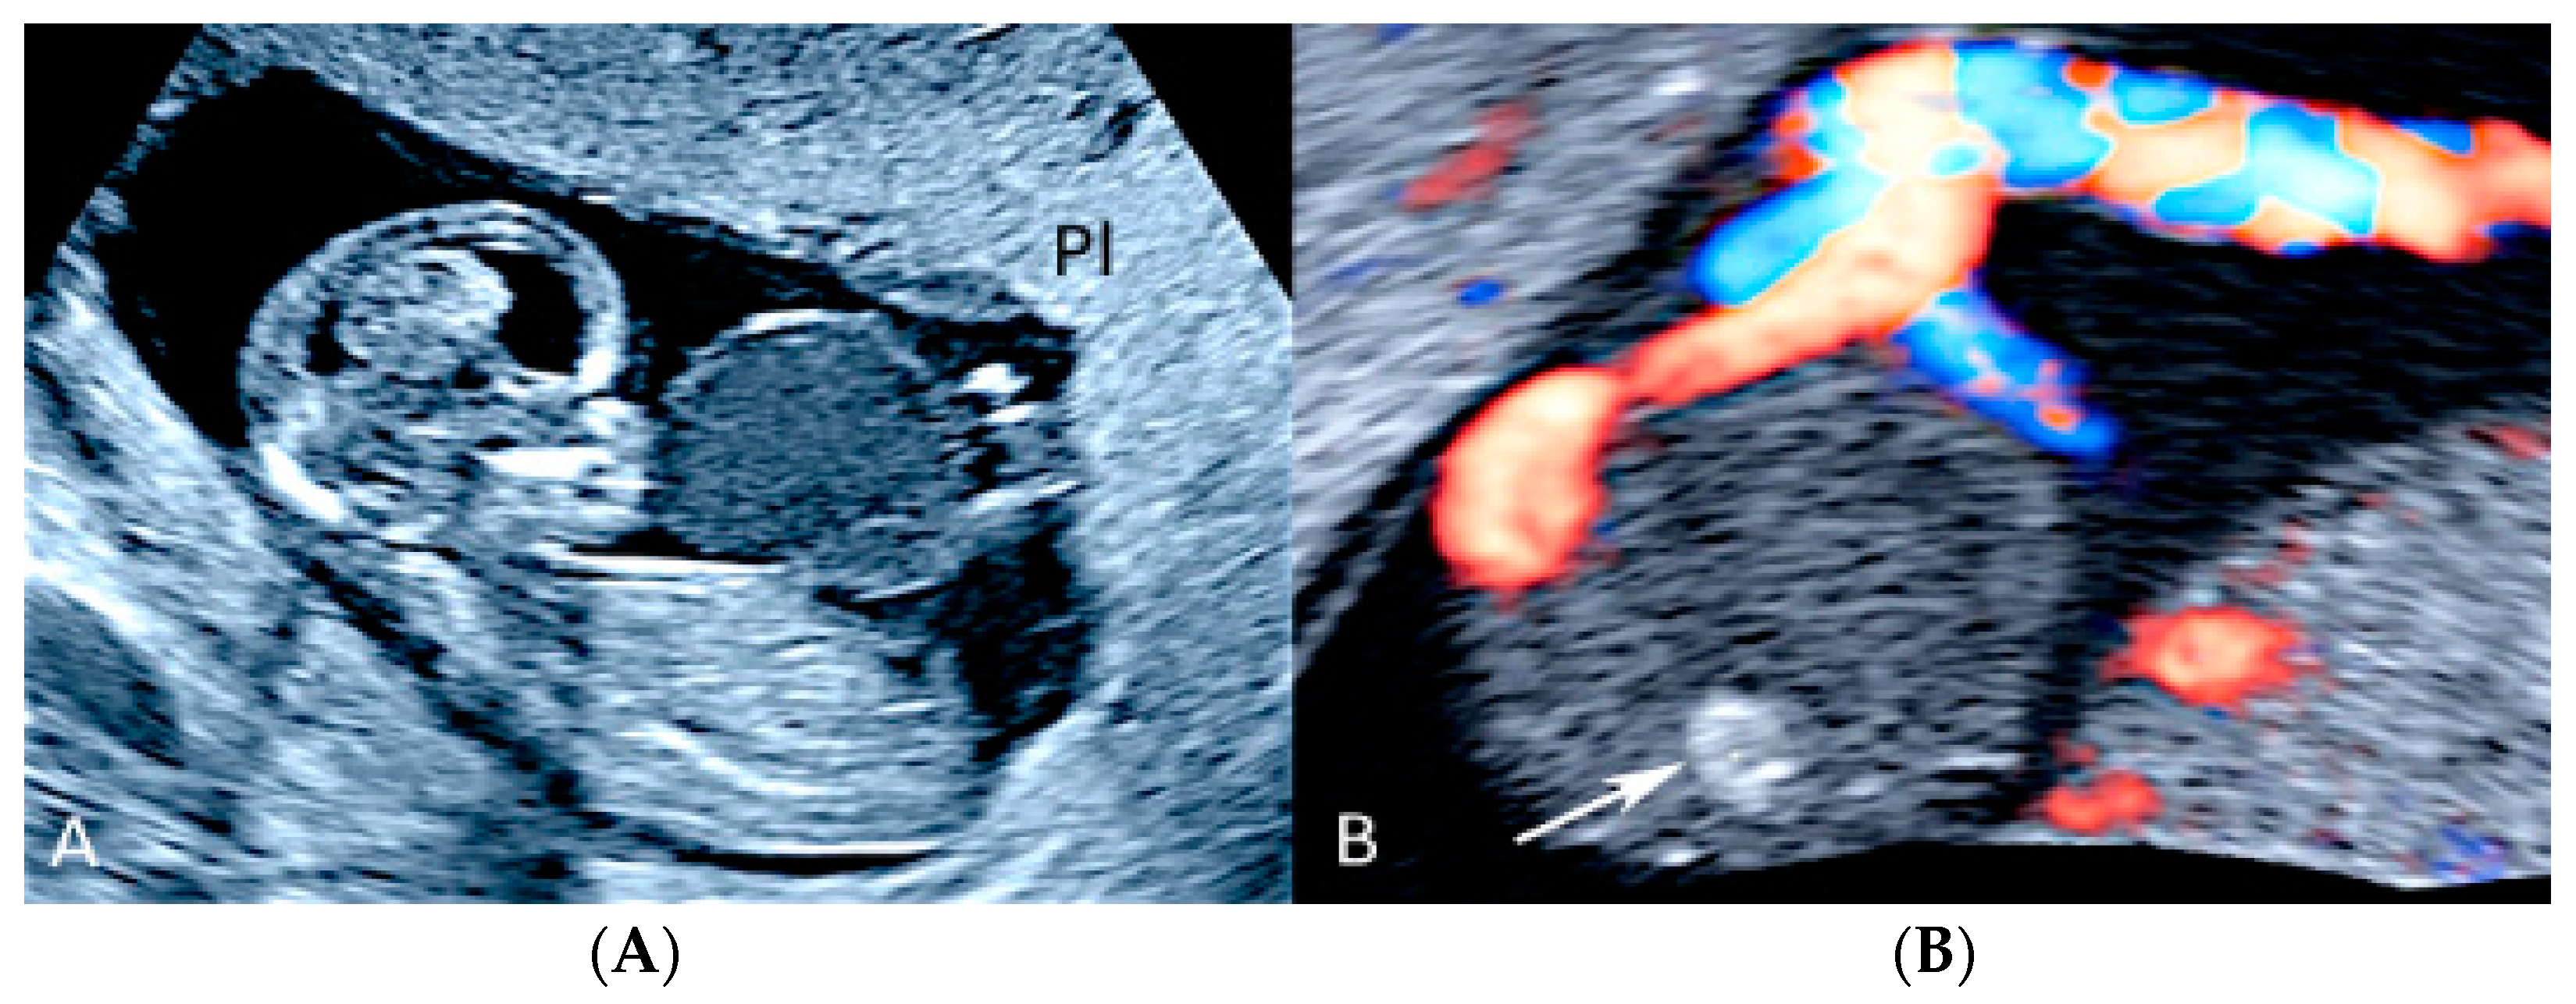

3.1.4. Circumvallate Placenta

3.1.5. Placental Mesenchymal Dysplasia